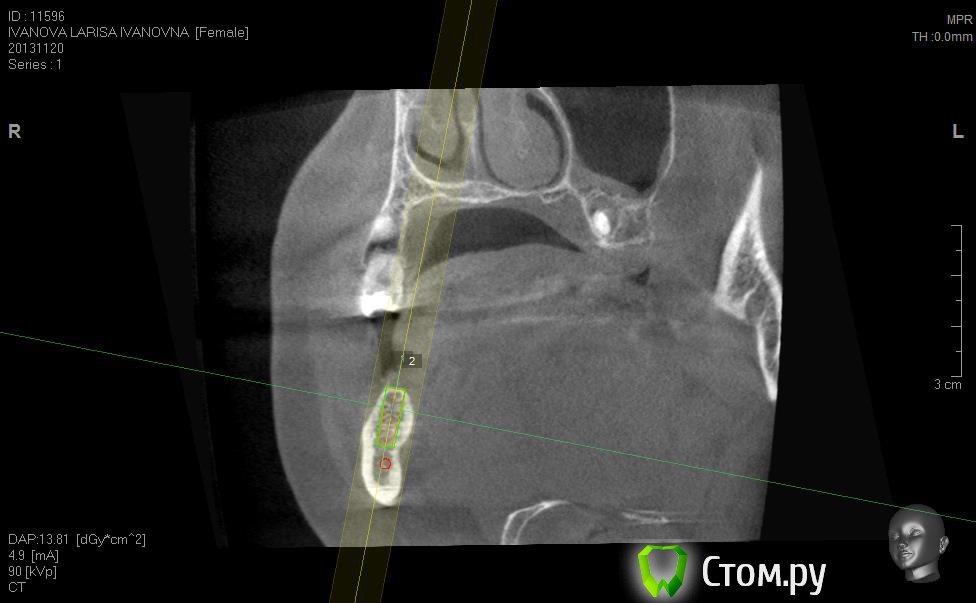

Neilrus Опубликовано 2 марта, 2014 Поделиться Опубликовано 2 марта, 2014 (изменено) Здравствуйте, коллеги, уделите 6 минут новичку…у меня тут проблема, она абсолютно не проблема для того, кто хоть пару раз делал расщепление гребня,а я вот только курсы закончил и у меня планируется через 7 дней операция. Вроде все понял, но пока стремаюсь.Посморите снимки, пожалуйста, а я напишу тот протокол, который хочу применить, как на курсах понял, поправьте, если что не так )) Спросил бы у лектора, но ведь так всегда, да?)Планирую иплантаты по месту 45,46 зубов.Гребень узкий в обл 45 з и близко нч нерв, как раз поднимается к ментальному отвертстию. С этим и связан страх. Никаких транспозиций делать пока не готов. В арсенале нет пьезотома пока, вот пару таких операций сделаю и куплю.Планирую поставить 4,2*8 для 45 зуба и 4,2*11,5 для 46 зуба (Мis Seven) . Соединю коронки, т.к. премоляр коротковат. Итак, план по захвату таков:1)Разрез чуть язычнее середины гребня, откидываем слиз-надк лоскут с аккуратностью в области менталиса.2)По центру гребня делаем горизонтальный распил сепарационным диском диаметром 7 не доходя до зубов по 3 мм. Глубина распила получается 3,3. Потом беру диск 10 и глубина уже 4,8.3)Мелким 7мм диском делаю дистально вертикальный распил на глубину 3,3 длиной с длину имплантата моляра 11,5, а медиально тем же диском на длину 4-5 мм, ниже страшно, боюсь нерв задеть. На верхушке гребня соединяем распилы (черные линии на моем рисунке). Делаем бором твердосплавным шаром компактостеотомию в преполагаемом месте перелома.4)Берем долото и вставляем в горизонтальный разрез и постукиваниями молоточка продвигаем его на глубину до 8мм по всей длине разреза (длина миниального импланта). Чуть покачивая из стороны в сторону, при этом убирая закругления от диска внутри горизонтального распила. (На рисунке, который сам нарисовал – это красная зона).5)Немного раздвинув края в месте предполагаемых имплантатов пилотом 2мм прохожу на глубину имплантатов. Проверяем параллельность.6)Загоняю по очереди мисовские компрессионные винты на глубину имплантатов до диаметра третьего винта 2,4- 3,7 (т.к. импланты 4,2)7)Теперь они вроде как должны быть нормально раздвинуты ( здесь я не понял, нужно проходить фрезами из хир набора или так хорошо войдут) Может финишной фрезой пройти хотя бы на всю глубину имплантатов? Подскажите, пожалуйста.8)Дальше заполняю пустоты MP3, фиксирую пинами MCT 2.75 мембрану evolution толстую на 2 мм ниже коспактостеотомии, перекидываю на язычную сторону под надкостницу краешек запихиваю.9)Мобилизую лоскут, ушиваю все наглухо и надеюсь на лучшее. ВОПРОСЫ:1)не коротковат ли имплант 4,2*8, но ведь я соединю их? Можно немного наклонить его медиально, выход шахты оставить там же, но апикальную часть ближе к моляру, тогда длина 10 выйдет, но там и так не получается соостно с зубами имплант размстить, а тут его и такая ангуляция, не хорошо, я думаю.2)Отслойка лоскута медиально- правильно я написал или порвется тогда и лучше рассечь связку на 44 и медиально вниз.3)Фрезы хирургические нужно использовать при нормальном раздвигании краев гребня? Кстати, нормально-это сколько для диаметра имплантата 4,24)Язычно нужно как-то дополнительно фиксировать мембрану?5)MP3 мешать с аутокостью и кровью из ловушки?6)Как лоскут мобилизовать медиально рядом с ментальным нервом? Пластика зкпд будет одновременно с открытием.Спасибо вам за ваше время ) Изменено 8 мая, 2014 пользователем Bier Ссылка на комментарий